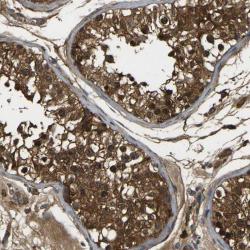

- Experimental details

- Immunohistochemical staining of human testis shows strong cytoplasmic positivity in cells of seminiferus ducts.

- Validation comment

- Staining pattern partly consistent with experimental and/or bioinformatic data.